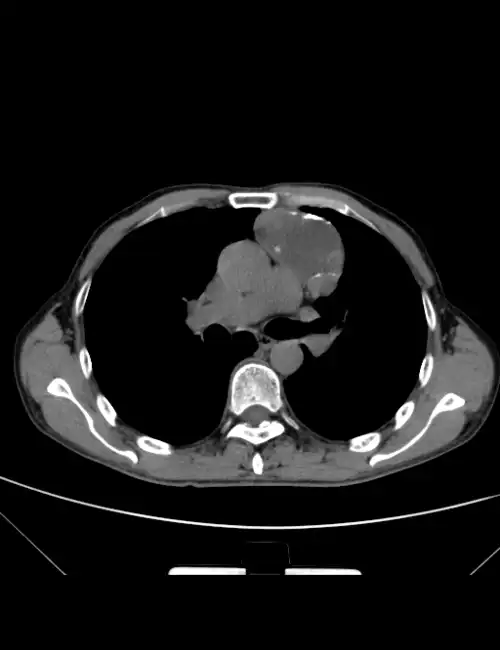

图3 ct平扫 增强

胸部ct平扫

外院ct平扫

ct平扫 三期增强,这个纵隔占位有点难 [病例帖]